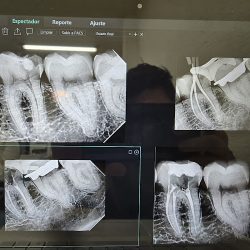

Dentistas en Ecatepec de Morelos

Dental Family Jardines De Morelos

Dental Family Jardines De Morelos se ha consolidado como una opción de confianza en Ecatepec de Morelos, destacándose por su… ver más

Dentista Aridentx

El Dentista Aridentx, ubicado en Ecatepec de Morelos, se distingue por ofrecer un ambiente acogedor y moderno, ideal para brindar… ver más